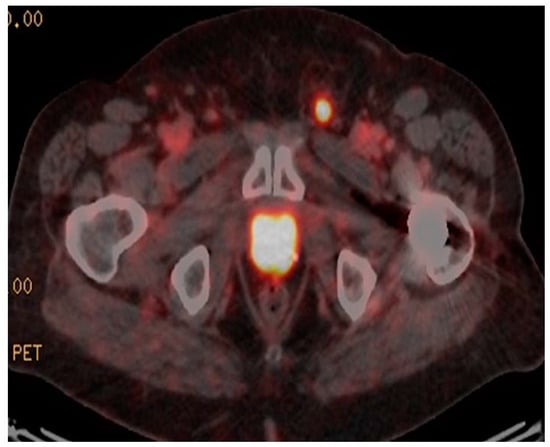

The earliest, and most extensive, experience with 68Ga-PSMA PET/CT imaging has been in the most common clinical scenario of biochemical relapse post-definitive primary therapy [60]. Up until the advent of 68Ga-PSMA PET/CT the mainstay of imaging included CT +/− bone scintigraphy and in some cases MRI [20]. The largest retrospective study of 1007 patients, reported detection rates for 68Ga-PSMA-11 PET/CT of 79.5%, in the setting of biochemical recurrence [61]. A recent meta-analysis revealed detection rates with 68Ga-PSMA PET/CT of 58% in patients with PSA between 0.2–1.0 ng/mL, 76% for PSA between 1 and 2 ng/mL and 95% for PSA > 2.0 ng/mL [62]. These findings reflect our own single institutional dataset utilizing 68Ga-PSMA I&T in 150 consecutive patients, where we have seen PSMA-avid disease in the setting of biochemical relapse in 25% of patients with PSA < 0.5 ng/mL. 67% of patients with PSA 0.5–1.5 ng/mL and in 92% of patients with PSA > 1.5 ng/mL [63]. Importantly, 68Ga-PSMA-I&T PET/CT reveals, in many cases, metastatic disease that is considered occult on CT, as demonstrated in Figure 1. In our dataset, statistically significant differences were seen between recurrent disease demonstrated by 68Ga-PSMA I&T and diagnostic contrast CT detection rates [63]. When compared with histological diagnosis, specificities of up to 100% have been detected in pre-surgical nodal assessment prior to nodal salvage surgery using 68Ga-PSMA [64,65]. A recent prospective Australian multi-center trial has shown that 68Ga-PSMA PET/CT leads to a change in management intent in 62% of patients with biochemical relapse, based upon the PSMA PET/CT scan result [66]. A separate study of 131 patients showed 68Ga-PSMA HBED PET/CT had a clinical impact in 76% of patients imaged [67].

Figure 1.

Rising PSA post-prostatectomy. PSA 0.9 ng/mL. CT unremarkable. 68Ga-PSMA-avid right pelvic lymph node.